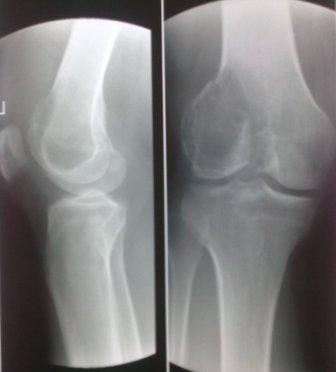

Уважаемые коллеги! Добрый вечер! Обратился мужчина 32 лет с жалобами на боли в обл. внутреннего мышелка левого бедра. Боли беспокоят около шести месяцев, лечился дома всякими мазями и т.д. 2 неделя назад упал , и после этого боли с каждым днем усиливаются. Местно определяется резкая болезненность в обл. мышелка бедра, явление не выраженного синовита, ограничение движения в коленном суставе, мягкотканый компонент опухоли не определяется, лимфоузлы не увеличены,Р-скопия легких без патологии,клинико-биохимические анализы в пределах нормы. Гистология- гигантоклеточная опухоль. Направил в онкологический центр, рекомендовали резекцию и ревизионное эндопротезирование коленного сустава, от которого больной отказался и опять вернулся к нам, временно фиксировали гипсовой повязкой. Уважаемые коллеги можно ли помочь больному, т.к. на практике были, что после перелома опухоль рассосалась и переломы срослись! Или может быть аутопластика и фиксация перелома? С уважением Абдурашид.

В доступной литературе мы не нашли подтверждения о спонтанном выздоровлении после (ОБК)- гигантоклеточной опухоли. В большинстве случаев данное заболевание путают с костной кистой, и грамотно проведенная дифференциальная диагностика поможет выбрать правильное решение.

Для костной кисты характерны более молодой возраст, овоидная форма, меньший размер, строго по оси, опухоль локализуется не в эпифизе, а в метафизе, поверхность гладкая, на 15% чаще чем при гигантоклеточной опухоли случаются патологический переломы. При патологических переломах тормозится дальнейший рост кисты и проблем со сращением не бывает.

Форма гигантоклеточной опухоли, вследствие ограничения ее роста суставной щелью, полуовальная или полуверетенообразная. Располагается асимметрично, крупноячеистая, размеры опухоли больше, густо костные балки, менее прозрачная на рентген снимках и на срезе грубо бугристая с продольными углублениями, как от сухожилий мышц.